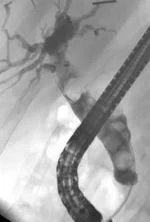

During ERCP, your doctor will pass an endoscope through your mouth, esophagus and stomach into the duodenum (first part of the small intestine). An endoscope is a thin, flexible tube that lets your doctor see inside your bowels. After your doctor sees the common opening to the ducts from the liver and pancreas, called the major duodenal papilla, your doctor will pass a narrow plastic tube called a catheter through the endoscope and into the ducts. Your doctor will inject a contrast material (dye) into the pancreatic or biliary ducts and will take X-rays.